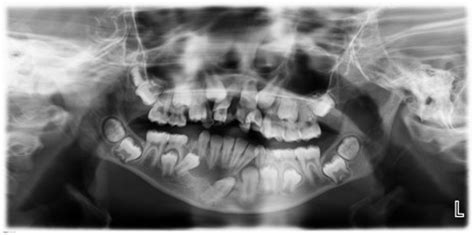

Panoramic X-Rays in Pediatric Dentistry

Panoramic X-rays are also valuable in pediatric dentistry, where they can help detect and monitor a range of issues in children and adolescents. Some of the key applications of panoramic X-rays in pediatric dentistry include:

• Tooth Development: Panoramic X-rays can help monitor the development of primary and permanent teeth, ensuring that they erupt correctly and on schedule.

• Impacted Teeth: Impacted teeth, such as wisdom teeth or canines, can be identified and assessed for potential extraction.

• Jaw Disorders: Temporomandibular joint (TMJ) disorders and other jaw-related issues can be detected and treated early to prevent further complications.

• Orthodontic Planning: Orthodontists use panoramic X-rays to plan orthodontic treatments, such as braces or aligners, ensuring that the teeth and jaws are properly aligned.